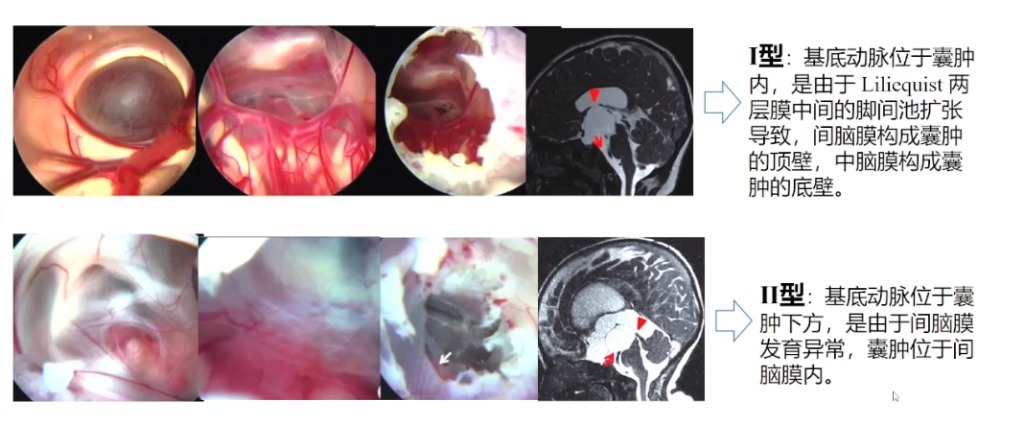

2.鞍上池囊肿分类——基于Liliequist膜机理

3.鞍上池囊肿分类——基于基底动脉位置